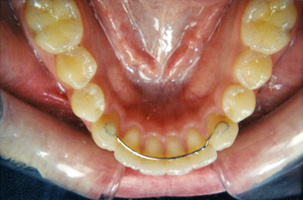

3. ΣΥΓΚΡΑΤΗΤΙΚΟΙ ΜΗΧΑΝΙΣΜΟΙ

Η συγκράτηση είναι η τελευταία και σοβαρότερη φάση της ορθοδοντικής θεραπειας. Στόχο έχει την  διατήρηση των δοντιών και των γνάθων στη νέα θέση. Οι συγκρατητικοί μηχανισμοί τοποθετούνται μετά την αφαίρεση των ακινήτων μηχανισμών. Χωρίς τους συγκρατητικούς μηχανισμούς τα δόντια μπορεί να μεταναστεύσουν πίσω στις παλιές θέσεις τους και το ορθοδοντικό αποτέλεσμα  να χαθεί εν μέρει. Οι συγκρατητικοί μηχανισμοί χρησιμοποιούνται με τη συχνότητα και την διάρκεια που θα υποδείξει κατά περίπτωση η ορθοδοντικός.

Τύποι συγκρατητικών μηχανισμών:

Νάρθηκας διάφανος αφαιρούμενος:

Αποτελείται από διάφανο πλαστικό. Είναι εύχρηστο και σχεδόν αόρατο.